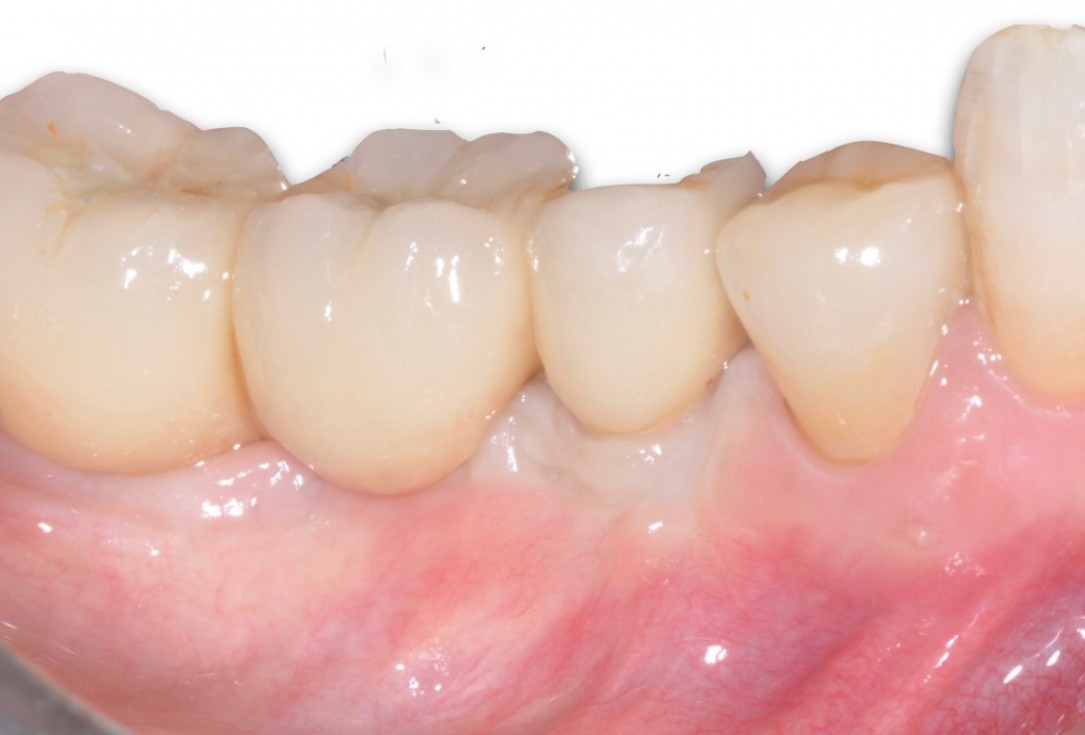

8/9 - Placement of a standard metal-ceramic bridgePeri-implant soft tissue augmentation for pontic with mucoderm® - Dr. M. Frosecchi